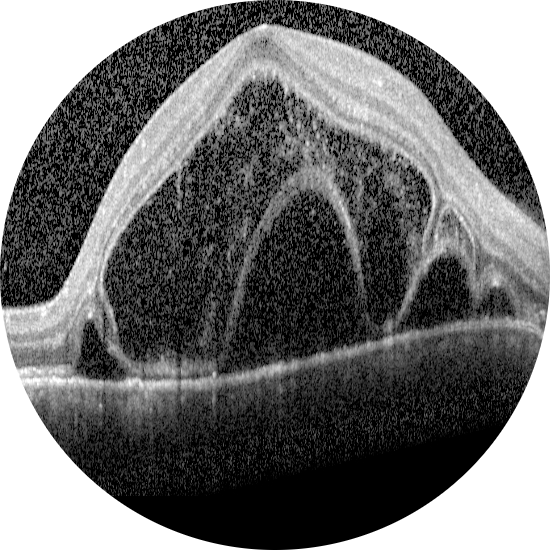

2026 Nisan Ayın Sorusu

Her iki gözde doğuştan bu yana görme problemleri olan 11 yaşındaki erkek hastanı ...